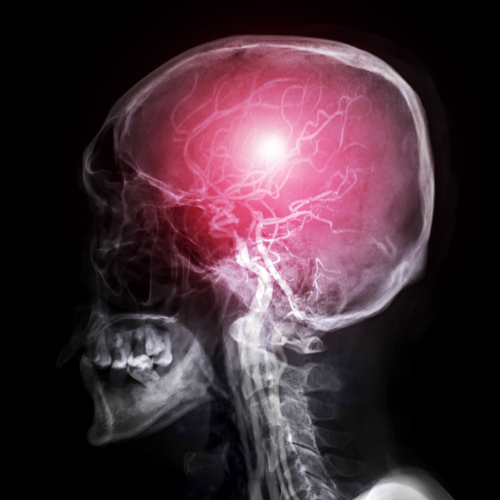

Chiari malformasyonu (yaygın adıyla Chiari sendromu), beyincik (serebellum) dokusunun kafatasının altındaki açıklıktan (foramen magnum) omurilik kanalına doğru sarkmasıyla karakterize yapısal bir bozukluktur. Normal şartlarda tamamen kafatası içerisinde yer alması gereken beyincik parçaları, kafatasının bu bölgedeki hacminin yetersiz olması veya şekil bozukluğu nedeniyle aşağı doğru itilir. Bu durum, hem beyin sapı ve omurilik üzerinde fiziksel bir baskı oluşturur hem de beyin omurilik sıvısının (BOS) doğal akışını engelleyerek merkezi sinir sistemi üzerinde çeşitli baskılara yol açar.